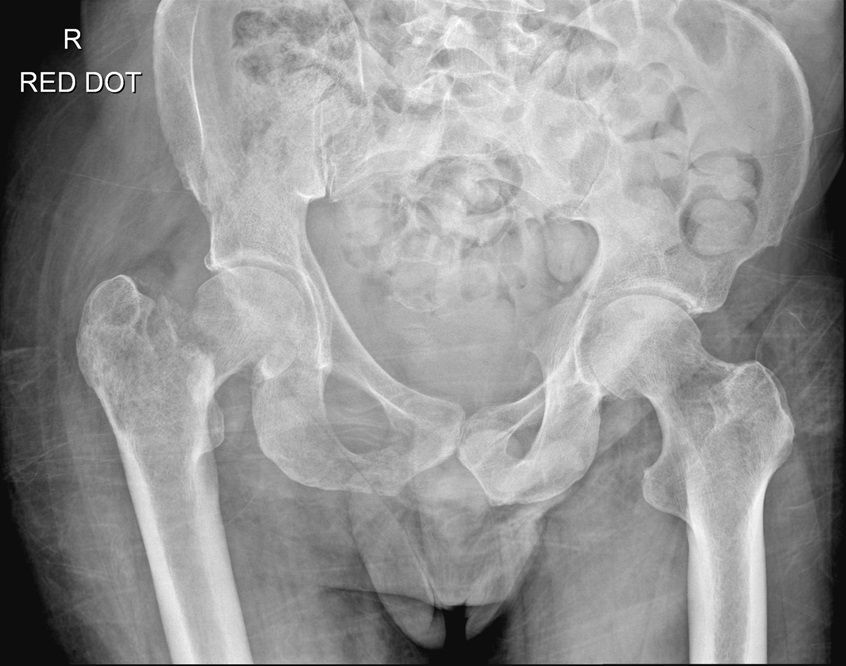

Question 4

Question

Which operation would you perform?

Answer

• THR

• Hemiarthroplasty